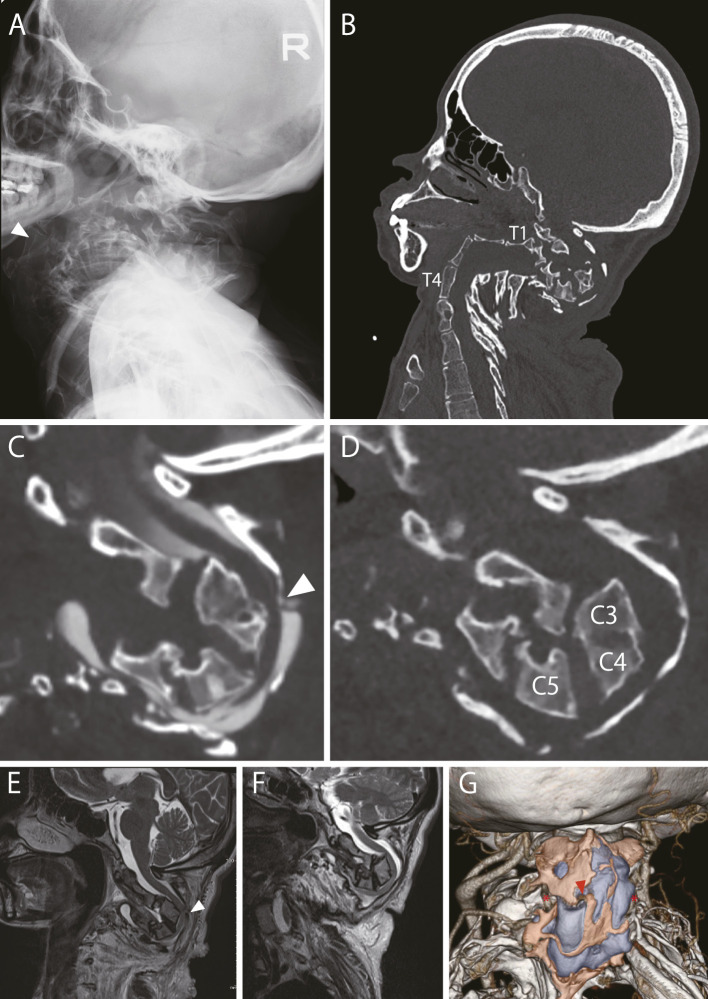

Treating Severe Cervical Deformity in Neurofibromatosis 1 with a Posterior Fibula Graft from Occiput to Thoracic Spine: A Case Report.

用枕骨到胸椎的后腓骨移植治疗神经纤维瘤病 1 的严重颈椎畸形:病例报告。